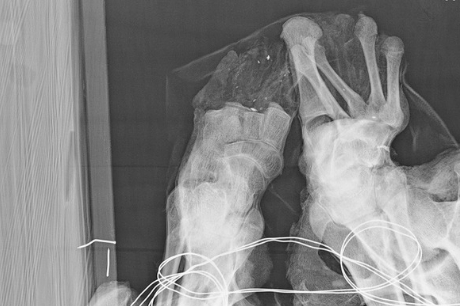

• His toes are missing, which could have resulted from excessive handling of the body post mummification. Alternatively, they may have been amputated due to infection or frostbite.

An X-ray of the mummy’s feet.